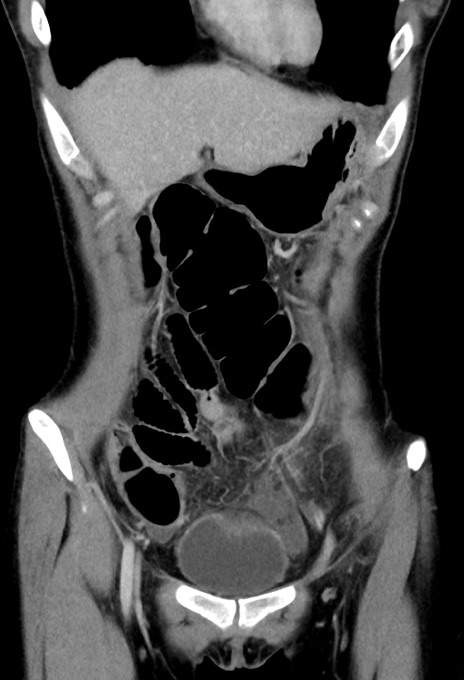

症例17(冠状断像)

【症例】20歳代女性

【主訴】嘔吐、下腹部痛

【現病歴】昨日夕食後に嘔吐し下腹部痛が出現。本日になっても嘔吐持続し改善しないため来院。

【身体所見】意識清明、BT 37.2℃、BP 108/67mmHg、腹部:平坦、やや硬、下腹部正中から右にかけて圧痛あり、反跳痛軽度あり、tapping pain(+)。

【データ】WBC 13600、CRP 14.94